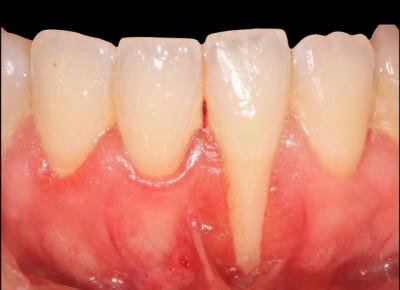

Technique de l’enveloppe : Incision séculaire en épaisseur partielle, mise en place du greffon dans l'enveloppe, sutures.

Technique de l’enveloppe : Incision séculaire en épaisseur partielle, mise en place du greffon dans l’enveloppe, sutures.